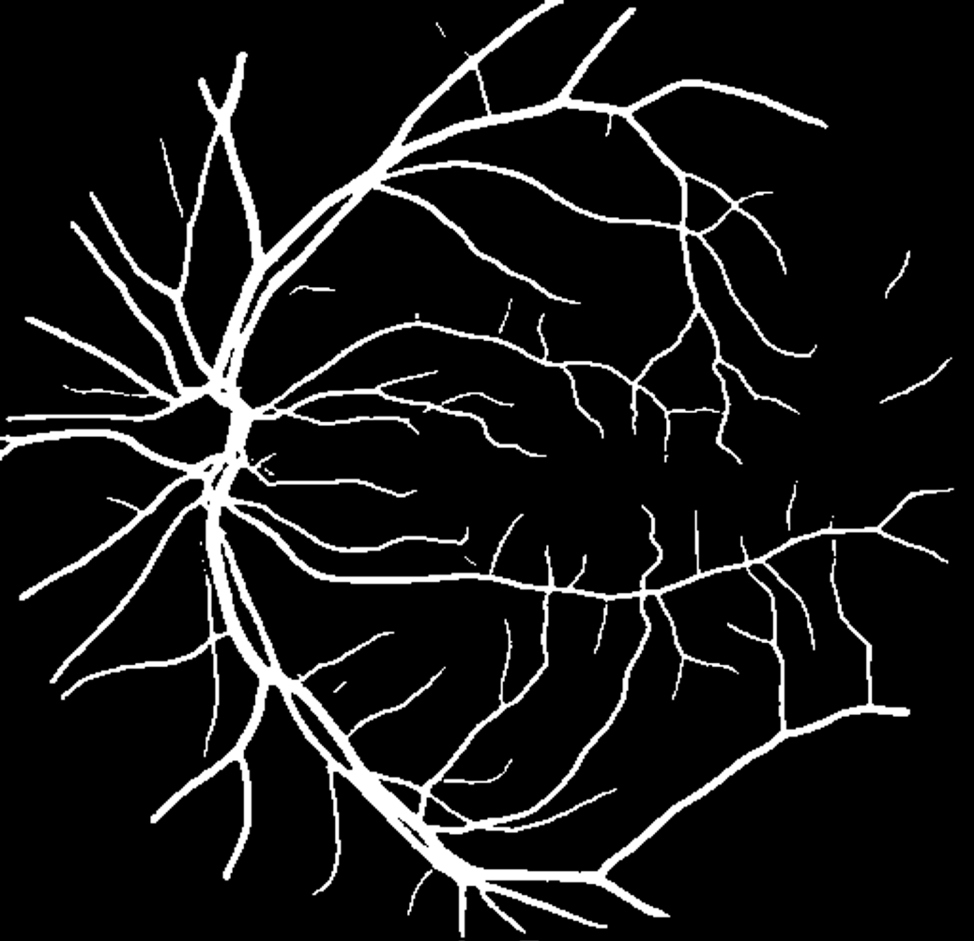

Starting with a fundus photo (Image 1), the AI identifies and maps retinal blood vessels (Image 2).

In image segmentation, AI learns to classify different pixels on a picture, based on what it represents.From there, we calculate a Tortuosity Score, a numerical value representing vessel curvature and complexity.

For example, a score of 1.21 quantifies the degree of twisting or bending within the vessels. Tracking this score over time could reveal subtle vascular changes before a clinical event occurs.